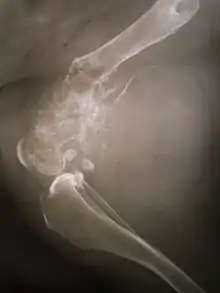

La tumeur peut être localisée à l'extrémité de l'os long. Le plus souvent, elle affecte l'extrémité proximale du tibia ou de l'humérus, ou l'extrémité distale du fémur. L'ostéosarcome tend à affecter les régions autour du genou dans 60 % des cas, dans 15 % des cas c'est autour de la hanche, 10 % à l'épaule et 8 % dans la mâchoire.

La tumeur est solide, dure, irrégulière, (décrite en « sapin » ou en « rayon de soleil » sur les examens aux rayons X) en raison des spicules tumorales d'os calcifiés rayonnant en angle droit. Ces angles droits forment ce que l'on appelle un triangle de Codman. Les tissus environnants sont infiltrés.